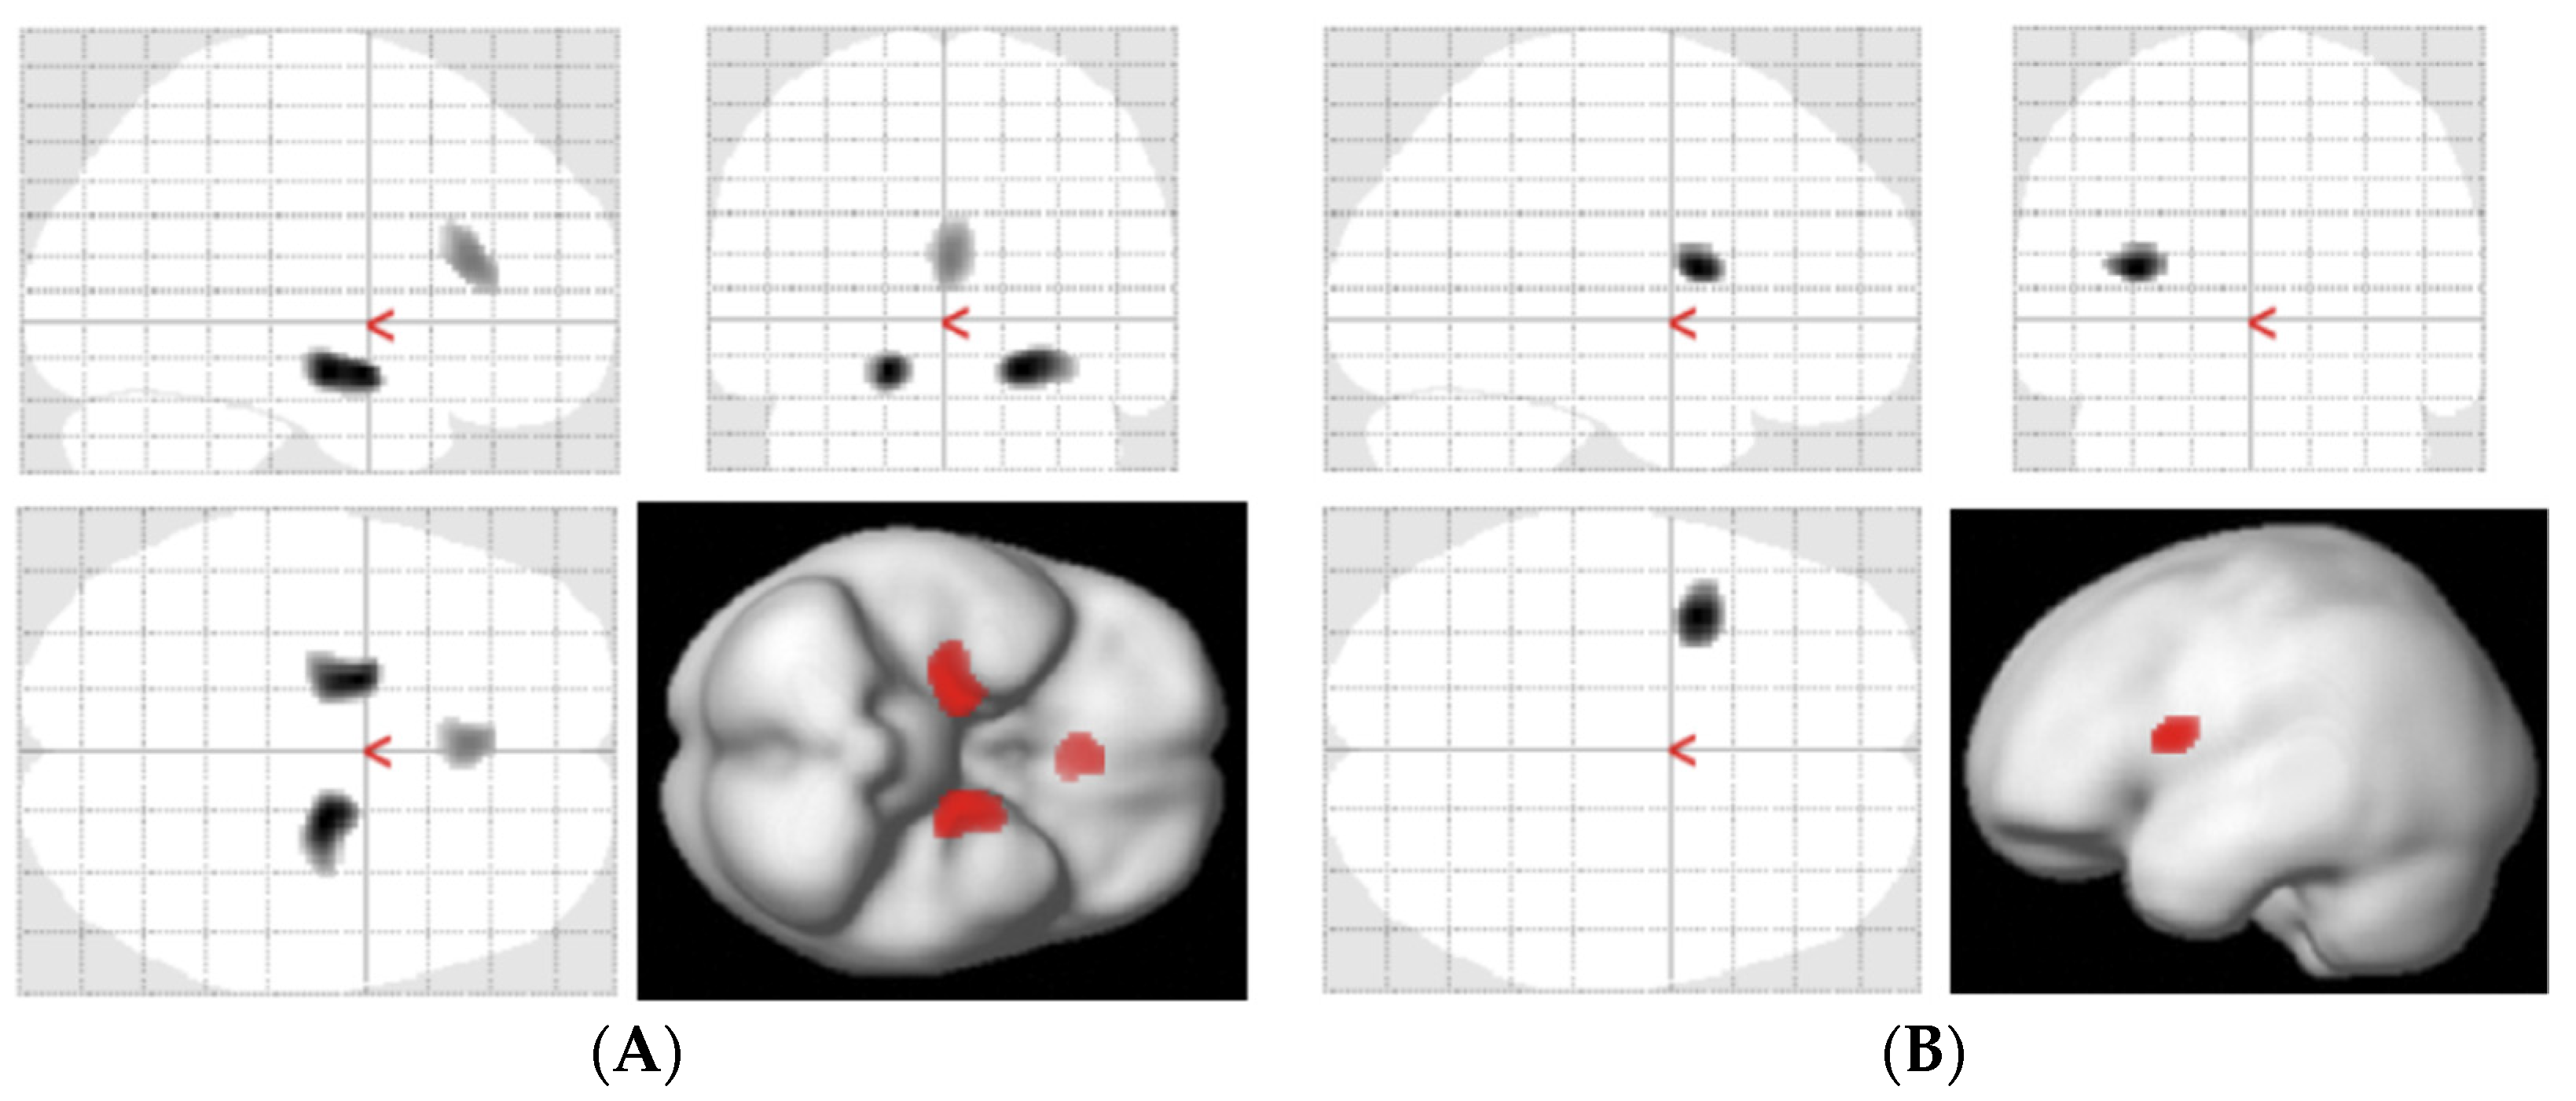

2.5. Statistical Analysis

- Braak, H.; Braak, E. Neuropathological stageing of Alzheimer-related changes. Acta Neuropathol. 1991, 82, 239–259. [Google Scholar] [CrossRef] [PubMed]